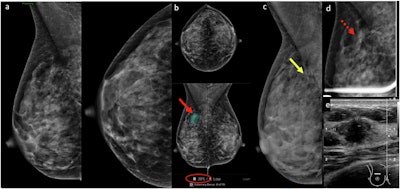

(a) Screening mammogram in a 44-year-old woman initially interpreted as normal by the radiologist on a particularly busy day. (b) Subsequent computer-aided diagnosis (CAD) analysis using Lunit INSIGHT MMG v1.1.7.1 annotated an isodense asymmetry with associated microcalcifications (red arrow) in the upper posterior right breast, seen on mediolateral oblique projection only. CAD flagged this area (red arrow) with a 38% likelihood of malignancy (red circle). (c) Retrospective review of a prior mammogram from a year ago revealed a small group of round microcalcifications in linear distribution (yellow arrow) in the area of CAD interest, not previously described. (d) Magnification imaging showed persistent asymmetry (dotted red arrow) with subtle architectural distortion and microcalcifications in the area of concern. (e) Ultrasound shows a corresponding irregular, nonparallel, hypoechoic mass with indistinct margins. Ultrasound-guided biopsy revealed grade 3 invasive ductal carcinoma.Chotai et al; Insights into Imaging